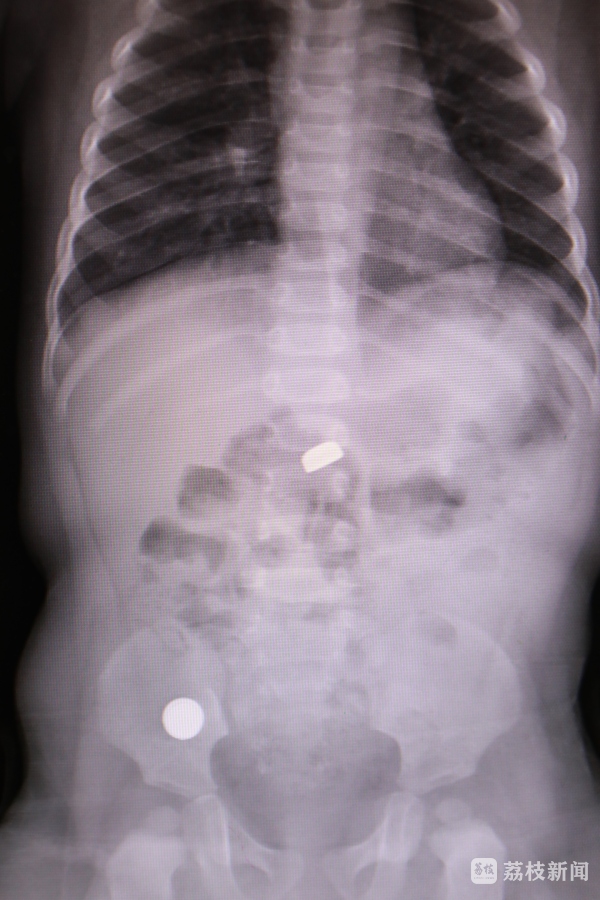

当晚,小天突然出现恶心、呕吐,还伴有腹痛,家人立即带其就医。医生查体发现,小天腹部发胀,有压痛和反跳痛,怀疑可能是异物所致。“做了腹部平片,发现腹腔里有两个光亮的影子。询问病史,家长高度怀疑是家里的纽扣电池被孩子吞了。”淮安市妇幼保健院小儿外科主治医师张岩说。

纽扣电池是低龄幼儿容易误吞误食的常见异物之一,同时它也是最具危险性的异物之一。电池中含有腐蚀性物质,如果电池在短时间内顺利排出还没有大的问题,一旦不慎卡在儿童身体内,数个小时后内容物就会不断流出,可能会造成消化道穿孔、引发腹膜炎、败血症,严重时甚至危及生命。由于不能明确电池误吞的时间,必须立即手术取出,避免危害升级。“术中发现,一颗电池位于十二指肠,另一颗位于小肠,两处都出现了发黑坏死的前期症状,再拖延下去,消化道就要穿孔了。取出来的电池已经有破损并且发生了泄露。”张岩说。